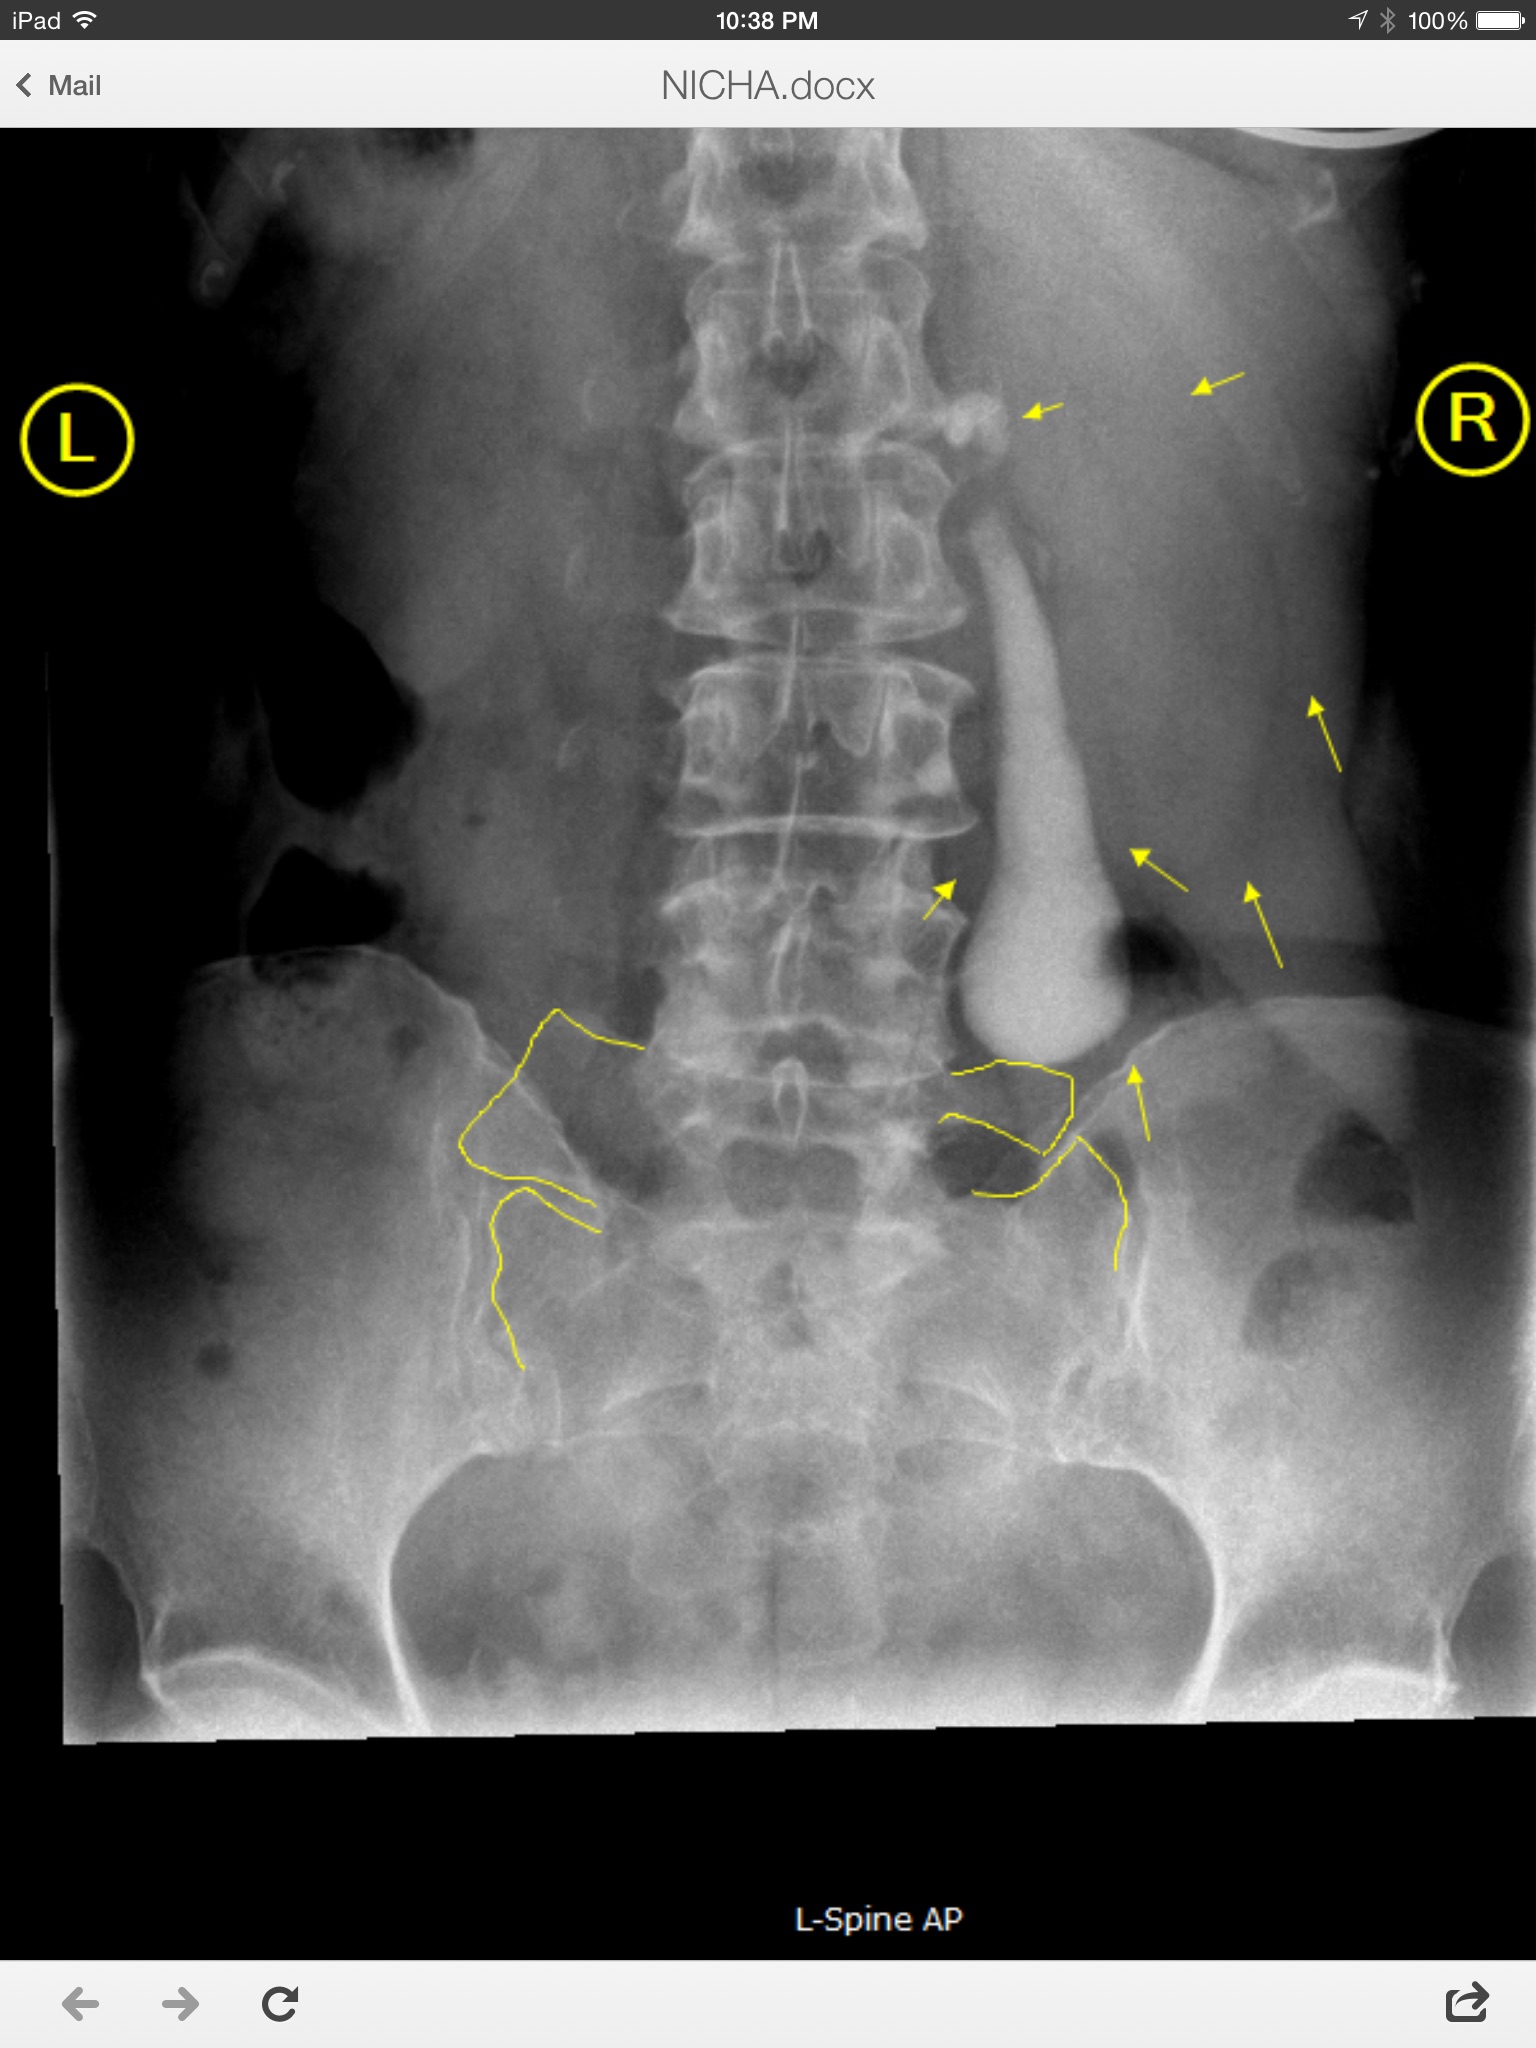

มีเพื่อนปวดหลัง ไปหาหมอจัดกระดูก เขาให้X-ray แล้วเจอสิ่งแปลกปลอมอยู่ข้างไต

นัดหมอประจำได้วันจันทร์ อยู่LAค่ะ ใจร้อนอยากรู้ว่ามันคืออะไร ใครมีความรู้ช่วยแนะนำหน่อยค่ะ ขอบพระคุณล่วงหน้าค่ะ